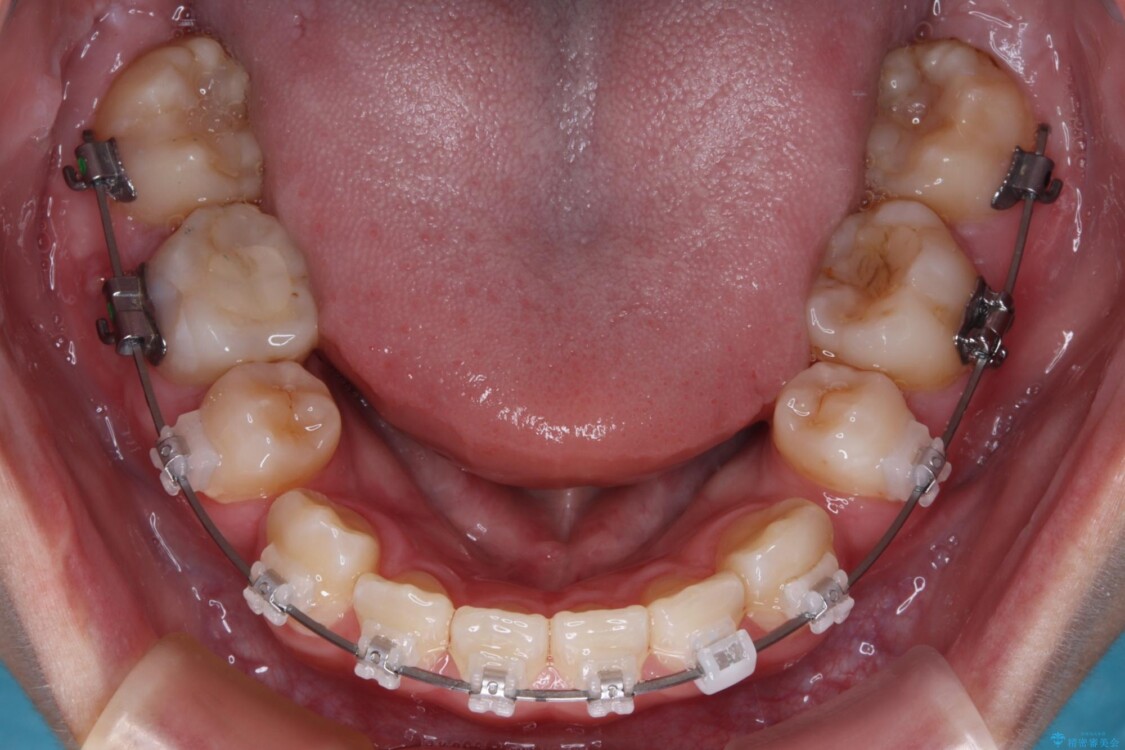

治療途中

• 転勤でも安心して治療継続 抜歯スペース閉鎖と深い噛み合わせ改善のワイヤー矯正 治療途中画像